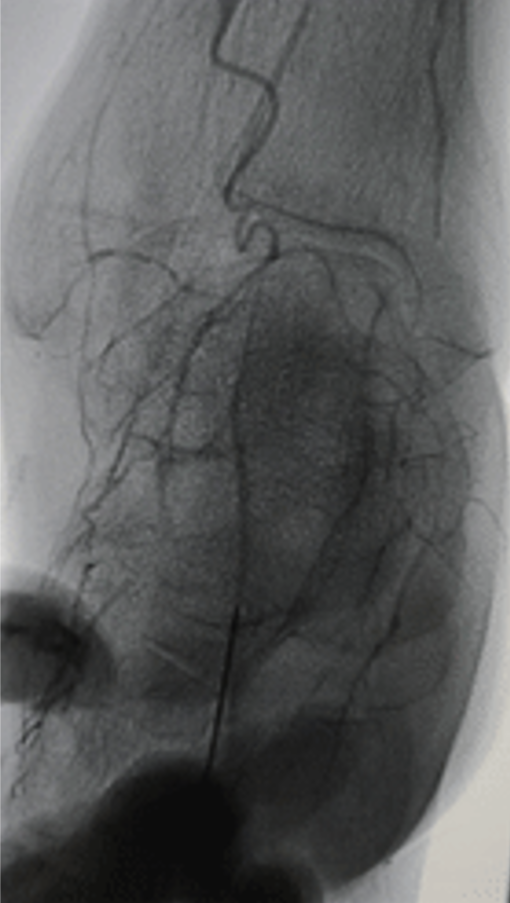

★ 第一足趾感染迁延不愈

Case 7:老年男性患者,第一足趾感染持续不愈达三月余。造影显示胫前动脉远端闭塞,胫后动脉缺如,腓动脉侧支供血不良。术者通过足弓将导丝送入第一足趾动脉,以1.5mm及2.0mm球囊逐级扩张。术后不足一月溃疡愈合,虽三个月后血管再闭塞,但感染未复发,随访两年稳定。

★ 足底外侧动脉的关键作用

Case 9:患者第三、四足趾不愈合,造影显示胫后动脉存在但足底外侧动脉缺如,足底内侧动脉不供应外侧足趾。术者开通胫前动脉后,经足弓将导丝送入足底外侧动脉进行扩张,最终实现足趾愈合。此病例提醒:足底弓的完整性不仅要看主干,还要关注分支动脉的供血范围。